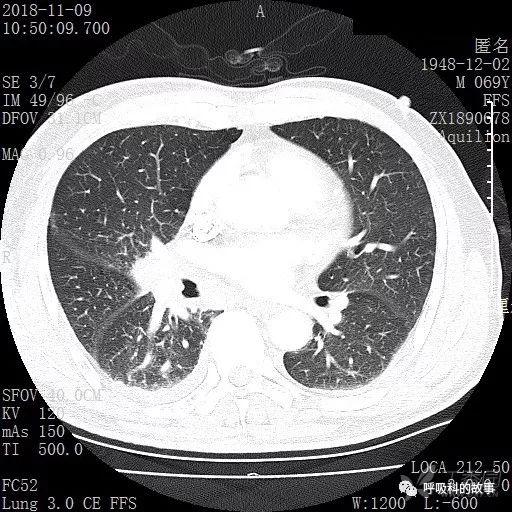

胸部增强CT示右肺门占位伴远端阻塞性肺炎,纵膈、右肺门、右侧颈根部、右侧腋下及肝门部肿大淋巴结。两侧胸腔少量积液。

纵隔窗的增强CT

肺窗CT